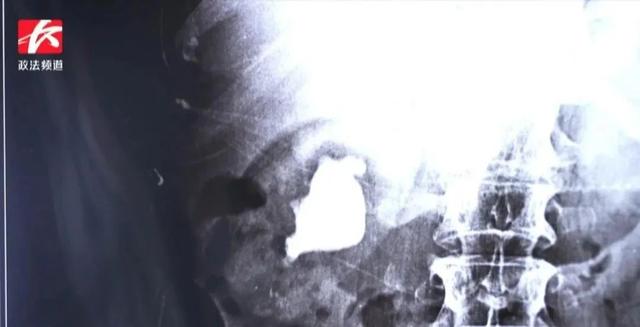

“无巧不成书,结石偏爱一家亲”,长沙59岁的肖女士家中兄弟姐妹9人无一幸免都患上了结石。其中,肖女士体内的结石如“大生姜”,严重威胁她的生命安全。

这一查发现,肖女士不仅患有左输尿管下段结石并左肾积水,右肾更是有一个大小约4cm形似“生姜”的铸型结石,情况危机,若不及时手术,肖女士肾脏功能面临严重损伤,后果不堪设想。